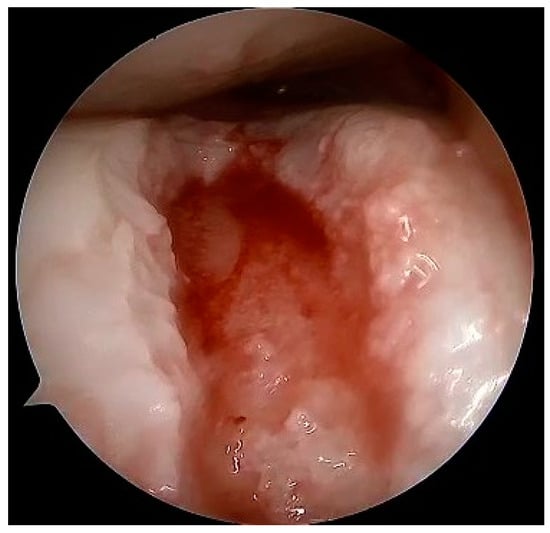

Figure 11.

Dry arthroscopy view of a full-thickness cartilage injury in the femoral trochlea after debridement and preparation for matrix implantation.

Figure 12.

Dry arthroscopy view of the same defect filled with cell-free matrix gel.